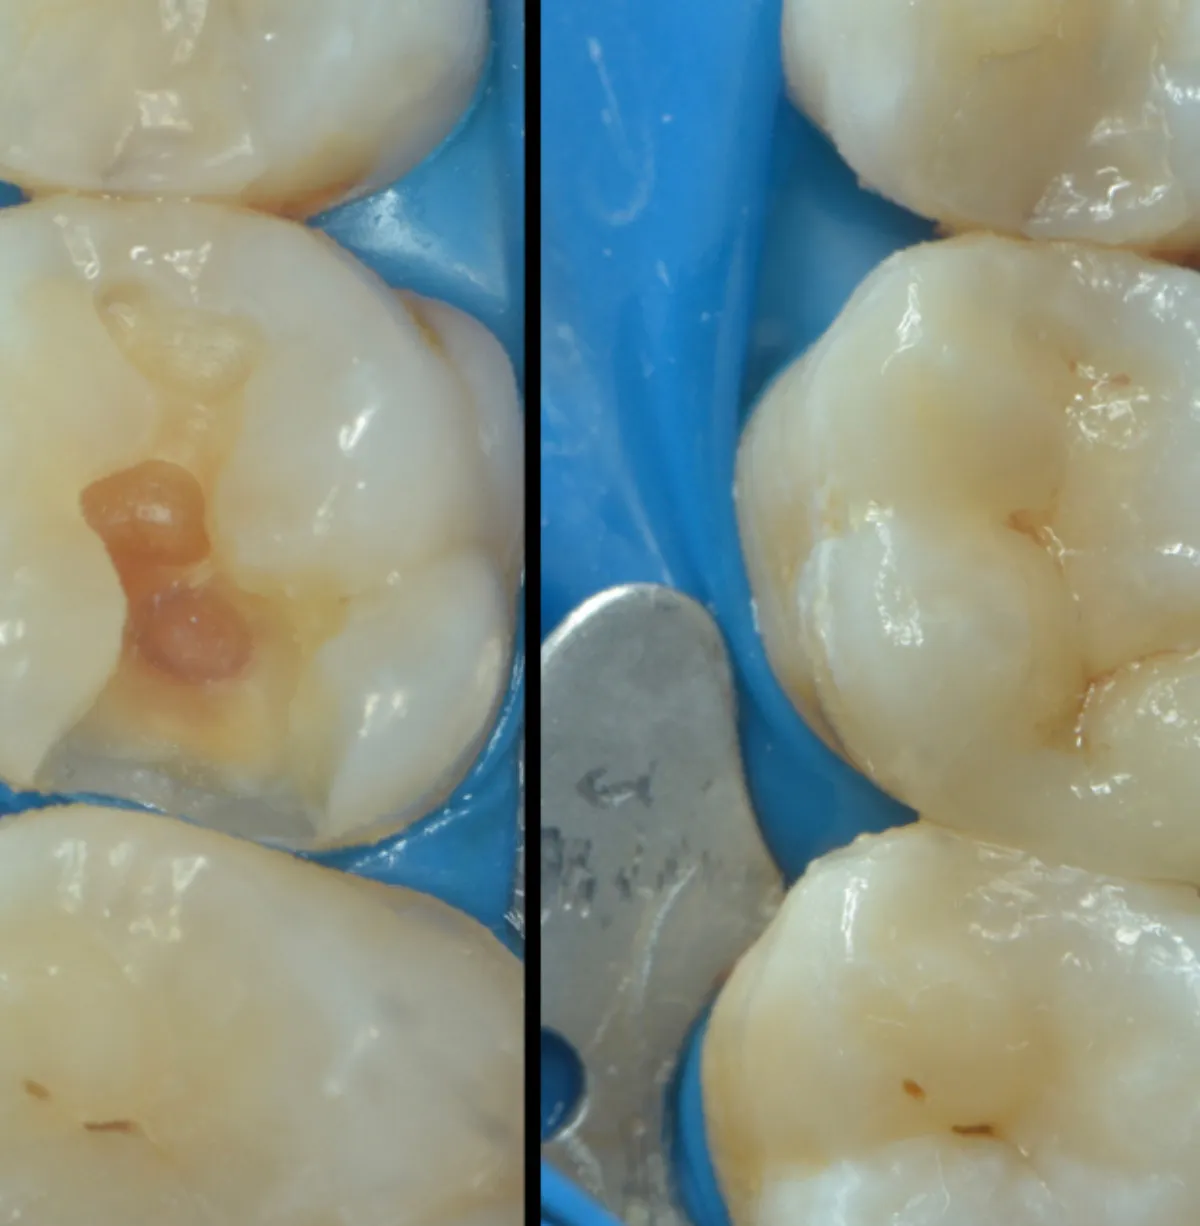

La Mb Dental, tratăm cariile prin obturații realizate sub microscop stomatologic, pentru precizie maximă, intervenții minim invazive și rezultate durabile.

La Mb Dental, tratăm cariile rapid, eficient și fără durere. Pornim de la diagnostic, trecem prin îndepărtarea țesutului afectat și ajungem la obturații estetice adaptate culorii dintelui, care refac forma și funcția naturală a acestuia.